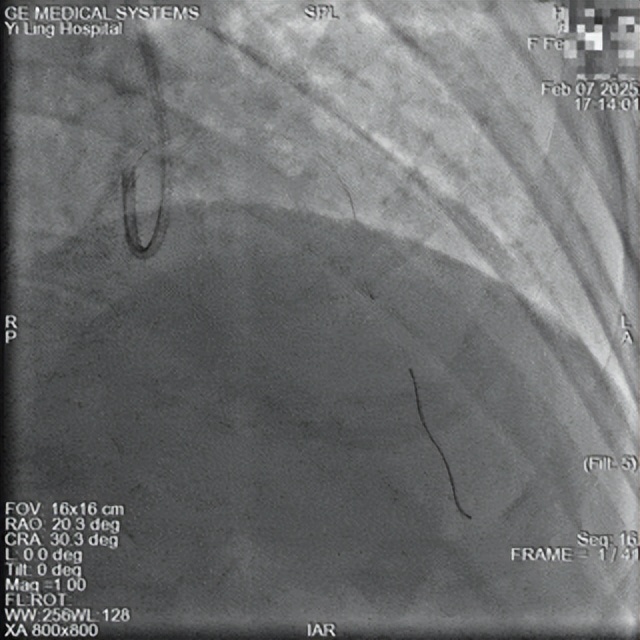

术前

一位64岁女性患者,因反复胸痛4天在当地诊所接受输液治疗后症状未见缓解,转入我院就诊。经心电图检查确诊为急性前壁心肌梗死。入院时胸痛持续,并发急性心衰,心脏彩超提示室壁瘤形成,病情危重。

心血管病科介入团队立即开展急诊救治。16时38分,急诊冠脉造影显示前降支100%闭塞伴血栓影。术中一度出现前降支远端血管无复流,团队迅速采取血栓抽吸、球囊扩张及导管内注射硝普纳等抢救措施。复查造影显示前降支残余狭窄<30%,未见夹层及撕裂影,前向血流恢复至TIMI3级。手术于17时14分顺利完成。